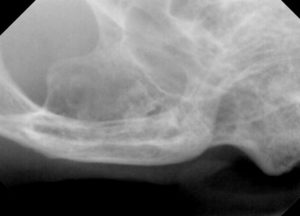

右側外観と下顎外観の写真は、この様な感じです。

ほどんどの歯はないのですが、肉眼でも残根らしき歯が認められ、周囲の歯肉が発赤しています。